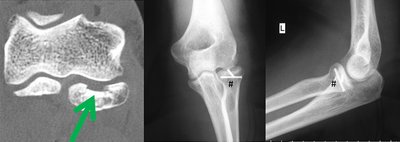

Osteochondrosis dissecans

Beim Heranwachsenden kann es zu Durchblutungsstörungen des gelenknahen Knochens kommen. Dies kann zu einer Ablösung des Knochens mit einem Knorpelschaden und einem freien Gelenkkörper führen.

Der Betroffene bemerkt Blockierungen des Gelenks und eine schmerzhafte Bewegungseinschränkung.

In frühen Stadien kann eine konsequente Reduktion der Belastung (Vermeidung des Stützens z.B. beim Turnen) die Erkrankung ausheilen. Sofern es immer wieder zur Blockierung des Gelenks mit Schmerzen kommt, ist eine minimalinvasive Therapie mit Refixation und ggf. Entfernung des freien Gelenkkörpers, der minimal invasiv entfernt werden kann, und die Behandlung des Knorpeldefekts angezeigt.